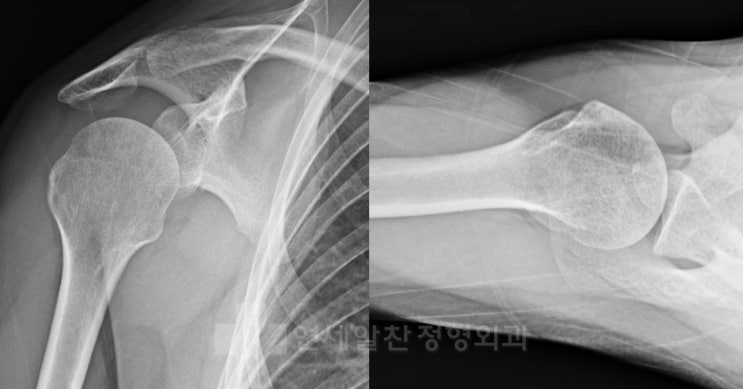

쇄골 원위부 골절에서 해부학적 금속판을 이용한 골절 수술

33세 남자환자로 스키 타다 넘어진 후 발생한 어깨 통증을 주소로 내원하였다. 골절 의심하에 X-ray 검사...